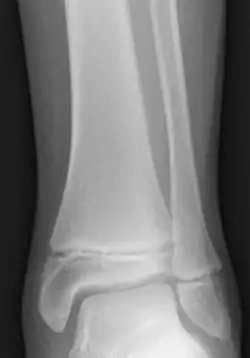

Salter–Harris fractures are fractures involving epiphyseal plates and hence tend to interfere with growth, height or physiologic functions.[12]